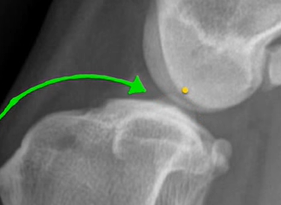

The centre of intercondylar eminences shown in Fig. 1;

The Medial Tibial Plateau line should be drawn using the first two.

Following the identification of points of interests, and drawing of the lines of interest, i.e. the Functional Tibial Line (FTL) and the Medial Tibial Plateau Line (MTPL), another line is drawn such that the relation of new line and the FTL is 90°. Tibial plateau angle is the angle between this new line and the MTPL; this is shown in Fig. 3.